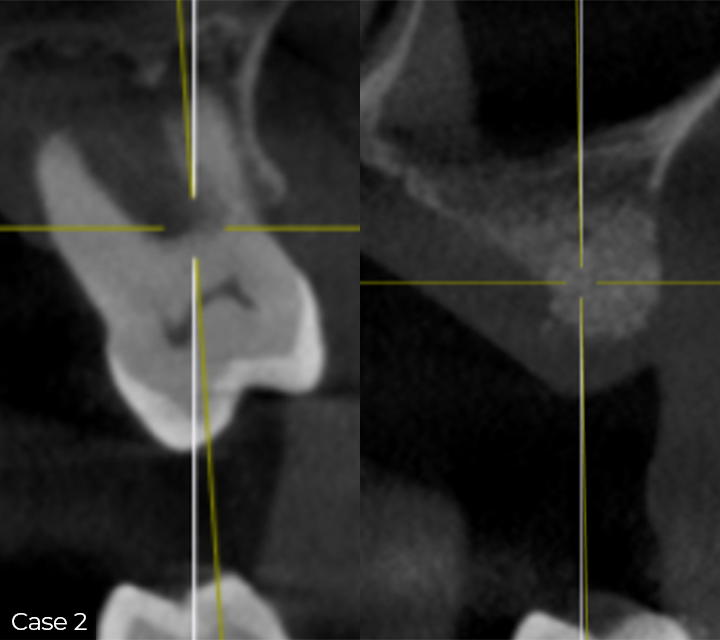

Director’s Clinical Cases

Director’s Clinical Cases